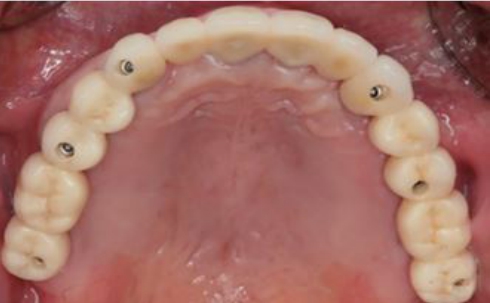

임플란트 지지 보철물은 골드, 레진치아, PFM crown, 지르코 니아 크라운 등 다양하게 사용되어 왔으나 최근 심미적이고 기능적인 면에서 우수한 지르코니아 크라운이 전치부 구치부 할 것 없이 대세를 이룬다고 하겠다(그림 13).

최근 digital techniology 의해 임플란트 보철물의 제작이 점점 증가되고 있지만 아직도 대부분의 임플란트 보철물은 인상채득에 의해서 모형위의 제작이 많은 것이 현실이다. 또한 최근 심미적이고 치주적인 관점에서 기성 abutment 에 비해 custom abutment가 많이 이용되고 있는 현실이다. 여기에서는 custom abutment를 위한 Fixture level 인상 채득 후 완성된 보철물의 장착을 위한 술식을 설명하고자 한다. 완성된 임플란트 보철물은 custom abutment를 이용하는 경우에, Abutment location Jig를 이용하여 구강 내에 Abutment를 장착한 후 보철물을 Bite stick을 이용해서 완전하게 seating시킨 후에 우선 인접치아와의 접촉정도 (자연치아 crown일 때보다 약간 tight한 것이 좋음)를 확인한 후 그리고 방사선 사진에서 fixture에 abutment가 잘 맞게 끼워졌는지 그리고 abutment와 crown간의 적합상태를 확인해야 한다(그림 15). 그 이후 교합관계를 확인 후 필 요하면 교합조정을 해야한다.